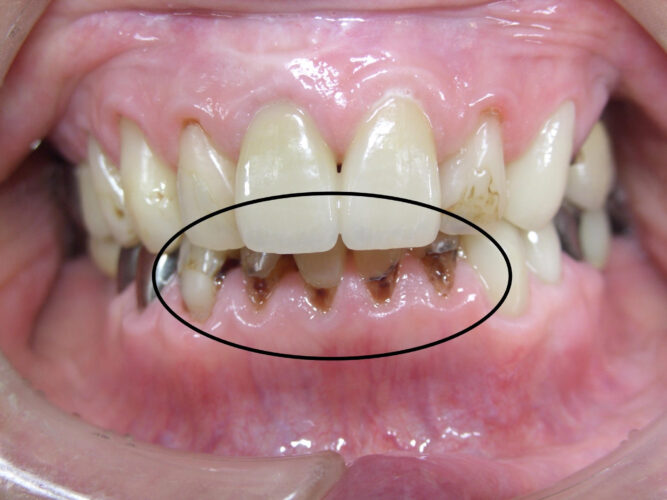

下の歯の歯ぐきの際が黒くなって、えぐれています。

残念ながら治療が必要な状態の「虫歯」です。

2年前の状態と比べて、明らかに虫歯が進行したのが分かります。